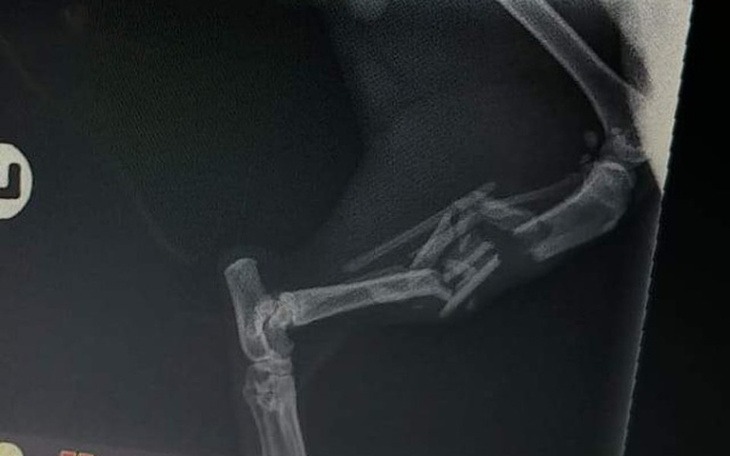

Jestem Patrycja, mam 14 lat. Rok temu przygarnelam 3 male koty z ulicy. Jednen ma na imie Puma. Jest to cudowny czarny kocur. Kociaki byly dzikie wiec musialy mieszkac na dworze bo w domu sie "dusily" wiec zostaly kotami podworkowymi. Dwa tygodnie temu Puma zaginęła, wracala raz na dwa dni na jedzenie A tydzień temu slad po niej zniknal. Dzis rano wrocila do domu na dwoch przednich lapach, tyln lapy maja zlamanie otwarte, biodro rozwalone a kosci sa pokruszone. Jedyne jakie szczescie ze kregoslup cały. Weterynarz powiedzial kwote 800 za operacje zeby miał gwoździe. Niestac mnie i mojej mamy zeby teraz dac taka kwotę. Dlatego bardzo prosze was o pomóc. Stawy sa doszczetnie rozwalone i maja w sobie rope, ten dzielny kociak wiedzial ze jak wroci dostanie pomoc. Dlatego teraz ja was bardzo pprosze o pomoc